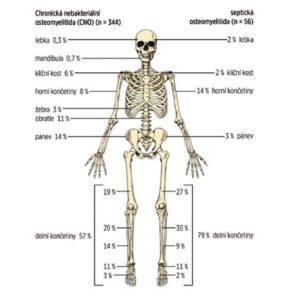

Najczęściej zajęte są przynasady kości długich, obojczyk, trzon kręgów i miednica (patrz rysunek nr 2). Liczba zmian kostnych jest zmienna (czasami tylko pojedyncze ognisko, częściej wielokrotne). Czasami bezobjawowe zmiany wykrywa scyntygrafia kości lub rezonans magnetyczny całego ciała (WB MRI).

Zdjęcie nr 2

Porównanie rozmieszczenia ognisk kostnych w badaniu MR dzieci z CRMO i septycznym zapaleniem kości (według Schnabel et al., 2016)